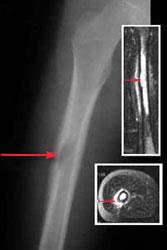

Bone tumor of the femur (thighbone)

Femur (thighbone) tumor. This X-ray shows a tumor in the middle of the thighbone. The tumor is also seen using magnetic resonance imaging (MRI) scan. The insert at top shows a coronal MRI. The insert at bottom shows a cross-sectional MRI. The arrows on all images show the location of the tumor.